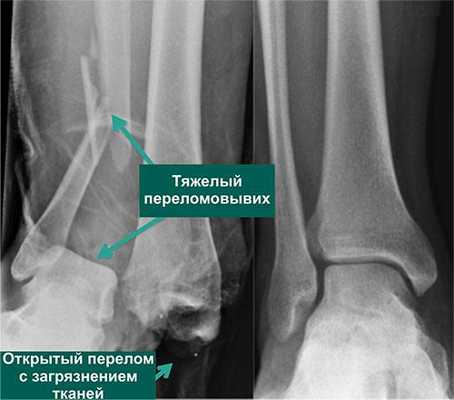

По статистике, 54% переломов и переломо-вывихов голеностопного сустава случаются в молодом возрасте, когда человеку важно сохранять трудоспособность. Эти травмы относятся к тяжелым повреждениям опорно-двигательного аппарата. Даже при качественном лечении они приводят к инвалидности в 3-12% случаев. Поэтому восстановление функций голеностопного сустава требует тщательного подхода, индивидуального для каждого пациента.

Каким способом врачи будут проводить лечение - зависит от тяжести травмы и характера повреждения сустава. Ведь надрывы связок лечить гораздо легче, чем, к примеру, переломы со смещением или переломо-вывихи. С лечебной тактикой специалисты определяются лишь после обследования пациента, имея полное представление о его состоянии и тяжести травмы.

- Хирургическое лечение. Проводится при застарелых повреждениях связок, посттравматическом остеопорозе, тяжелых переломах и переломо-вывихах. Позволяет восстановить функции голеностопа даже тогда, когда другими путями сделать это невозможно.